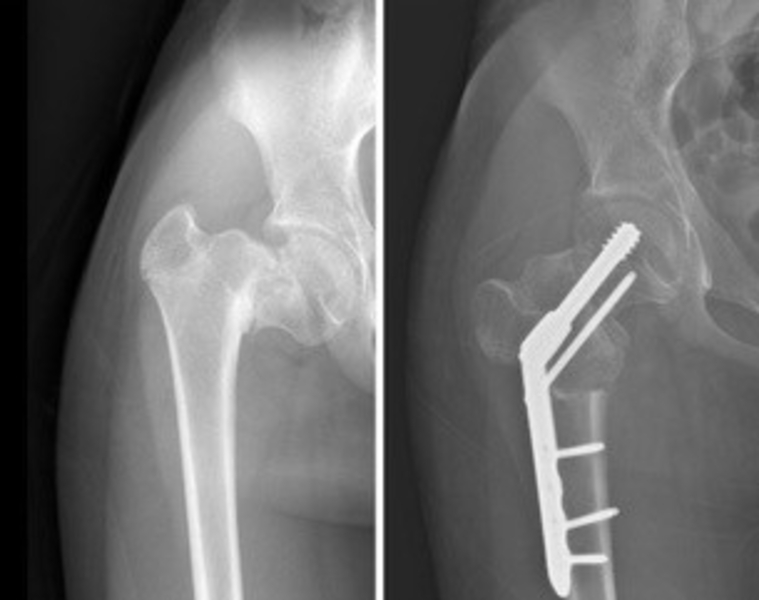

A pediatric orthopaedic surgeon at USA Health is the first provider in Alabama to use a new pediatric hip implant and one of the first in the nation to use the implant to repair a fracture and reposition a bone in the same procedure. In October, Dr. William Cutchen, a pediatric orthopaedic surgeon at USA Health, used the new 3P Pediatric Plating Platform Hip System to repair a rare femoral neck fracture in an adolescent girl’s hip at USA Health Children’s & Women’s Hospital. The patient also had a deformity in the same hip known as coxa vara due to a previous fracture. The implant allowed Cutchen and the operative team to address the fracture and deformity in one setting. Correcting the deformity also reoriented the fracture to be in a better position to heal. The new hip implant includes a beam screw construct and locking proximal femur plates and comes in infant, child and adolescent sizes. The technology improves precision and offers surgeons several ways to stabilize the bone during both injury repair and correction of the bone shape. One of two pediatric orthopaedic surgeons at USA Health, Cutchen sees patients at the Strada Patient Care Center and performs surgery at Children’s & Women’s Hospital, both in Mobile.